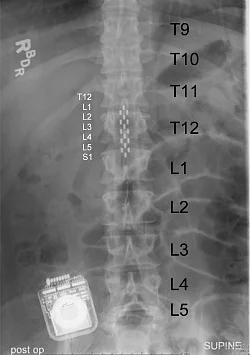

Electrical leads implanted in the paraplegic patient (Image: Medtronic, Inc.)

Implanted electrode array (Image: The Lancet)